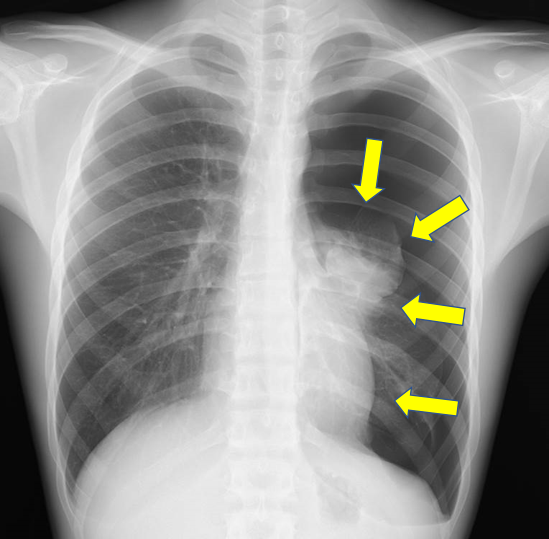

【2023年最新】胸腔ドレーンの看護|仕組み・管理やエアリーク・抜去・観察項目 ナースのヒント